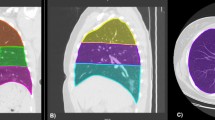

All images were interpreted independently by two radiologists with 18 years (Y.O.) and 4 years (H.E.) of experience, respectively, in clinical radiology. CT images were evaluated for the following: lesion distribution (single/both lungs, central/peripheral), presence of GGOs, consolidation, air bronchogram, crazy paving pattern, subpleural line, bronchial wall thickening, bronchiectasis, pleural thickening, cavitation, CT halo, reversed halo, pleural effusion, pericardial effusion, pulmonary emphysema, pulmonary fibrosis, and hilar and/or mediastinal lymphadenopathy. In addition, each lobe of the lung was assessed for opacification, and the lesion size was graded as follows: 0 (none), 1 (< 1 cm), 2 (1–3 cm), 3 (3 cm to < 50% of the lobe), or 4 (50–100% of the lobe). The score for each lobe was summed to produce a total score ranging from 0 to 20 [10, 11]. This total score was categorized into three groups: (1) ≤ 10 points, (2) 11–15 points, and (3) 16–20 points.

Among 269 patients for whom CT images obtained at the time of admission were available, the most frequent findings in severe cases were GGO, followed by bronchiectasis, air bronchogram, subpleural line, crazy paving pattern, consolidation, and bronchial wall thickening (Fig. 1). Abnormalities were distributed in the peripheral region, but in severe cases, they also spread to the central region, and in most cases, this was observed bilaterally (Fig. 2). While one case had pulmonary edema and another had aspiration pneumonia, all cases had lesions due to COVID-19 pneumonia; Fig. 3 shows two representative cases with such lesions on CT. In non-severe cases, GGO was observed in the peripheral region (Fig. 3a), but was also found in the central region in some patients (Fig. 3b). Elevated total scores were observed in severe cases (Fig. 4; see also Supplementary Table 1). Severe cases presented high scores in not only the lower lobes but also the upper lobes (Supplementary Table 1). The total score groups were associated with severe disease in a dose-dependent manner as shown by the increase in the crude ORs with increase in total score (Table 4, top). The OR adjusted for sex and age (aOR) showed similar results; adjusted for sex, age, and hospital size, the associations of the CT scores remained the same. In addition, when the total score was treated as a continuous rather than categorical variable, the OR increased by 1.5 (95% CI = 1.3–1.7) for every 1-point increase in total score, and increased by 1.4 (95% CI = 1.2–1.6) when adjusted for age, sex, and hospital size. In the ROC analysis of the total score, the AUC was 0.93 (95% CI = 0.89–0.98) and an optimal cut-off score of 11 was found to predict severe disease with 90.9% sensitivity and 82.2% specificity.

COVID-19 chest CT and X-ray images on admission. a Chest CT image of a 68-year-old male patient with ground-glass opacities (GGO) in the peripheral region (non-severe case). b Chest CT image of a 51-year-old male patient with GGO in the peripheral and central regions (non-severe case). c Anterior–posterior (AP) chest X-ray image of a 70-year-old female patient with cardiomegaly (severe case)

Among 168 cases for which chest X-ray images obtained at the time of admission were available, the common findings of severe cases included reticular-nodular opacities, cardiomegaly, and consolidation (Fig. 3c and Fig. 5). In particular, high CTR values were observed in both PA and AP views of severe cases (Fig. 6) and cardiomegaly was strongly associated with severe disease [OR = 52.1 (95% CI = 13.0–208.4); aOR for sex, age, hospital size, and patient positioning of chest X-ray = 24.6 (95% CI = 3.7–166.0)]. For cardiomegaly, a case was excluded from the calculation due to insufficient information to classify to PA or AP. Abnormalities were distributed in both lungs, in each zone, and showed a basal predominance (Fig. 7; see also Supplementary Table 2). High total scores were also observed in severe cases (Fig. 8; see also Supplementary Table 2). The total score groups were associated with severe disease in a dose-dependent manner (Table 4, bottom, crude OR), and the aOR controlling for sex and age showed similar results. In addition, adjusted for hospital size, the association remained similar between severe disease and chest X-ray score. When the total score was treated as a continuous rather than categorical variable, the OR increased by 1.2 (95% CI = 1.1–1.2) for every 1-point increase in total score, and the aOR increased by 1.1 (95% CI = 1.0–1.2), after adjustment for sex, age, and hospital size. An ROC analysis of the total score revealed that the AUC was 0.91 (95% CI = 0.86–0.97) and an optimal cut-off value of 9 predicted severe disease with 83.3% sensitivity and 84.7% specificity. Considering the presence of cardiomegaly on admission, for patients without cardiomegaly on admission, a high chest X-ray score of ≥ 9 showed a strong association with severe disease (crude OR = 44.1; 95% CI = 5.1–377.7; aOR controlling for sex, age, and hospital size = 11.7; 95% CI = 1.1–119.5). In patients with cardiomegaly on admission, a high chest X-ray score was not associated with severe disease (crude OR = 1.3; 95% CI = 0.1–20.7).